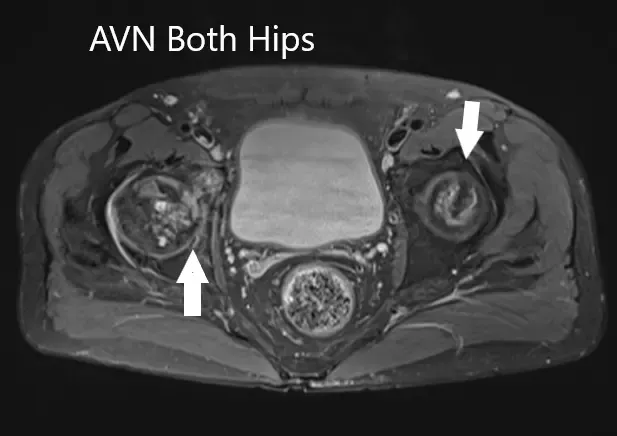

La resonancia magnética sugirió una marcada atenuación de señales en las cabezas femorales bilaterales. Hubo un colapso de la cabeza derecha y un precolapso en la etapa 2a de la cadera izquierda.

La resonancia magnética muestra un AVN bilateral femoral en T2WI

Secciones axiales de T1WI y T2WI que muestran AVN bilateral de las cabezas femorales